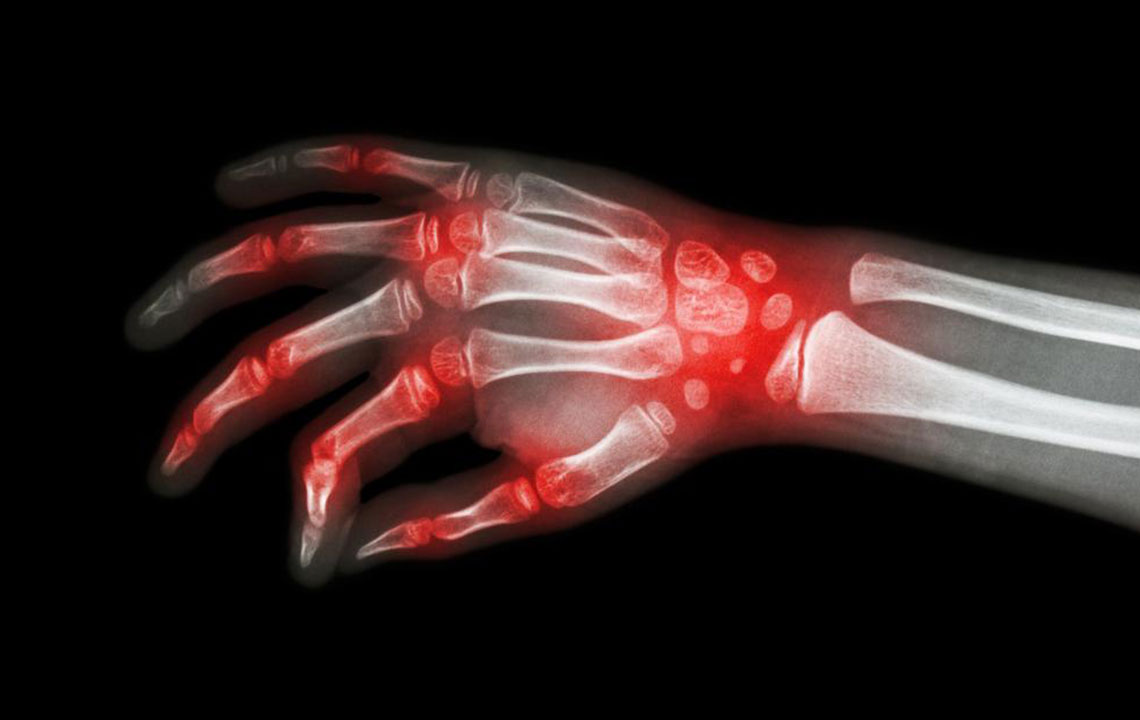

Lupus and rheumatoid arthritis are both autoimmune conditions that are often confused to be the same. The fact that these – rheumatoid arthritis, lupus are autoimmune diseases makes their symptoms similar too. Auto immune diseases are typically those conditions where the immune system of the body attacks healthy cells, causing inflammation, swelling, and pain in the affected areas. There can be various triggers for the immune system of the body to react in both these diseases, but there is no single related cause for these auto-immune disorders.

The most shared and evident similarity that rheumatoid arthritis and lupus share is joint pain.

However, the levels of inflammation and swelling of joints may vary between these conditions. Joint pain is also a common symptom of patients diagnosed with either rheumatoid arthritis and lupus. Also, the joints can become warmer and tender, though this is a more prominent symptom of rheumatoid arthritis.

It is these similarities that cause a lot of confusion with the diagnosis of rheumatoid arthritis and lupus. There are several times when patients are diagnosed with rheumatoid arthritis when they actually have lupus. This usually happens in the early stages of the disorder. As the condition progresses, the difference becomes evident; rheumatoid arthritis causes bone deformity and erosion while lupus rarely leads to bone erosion.